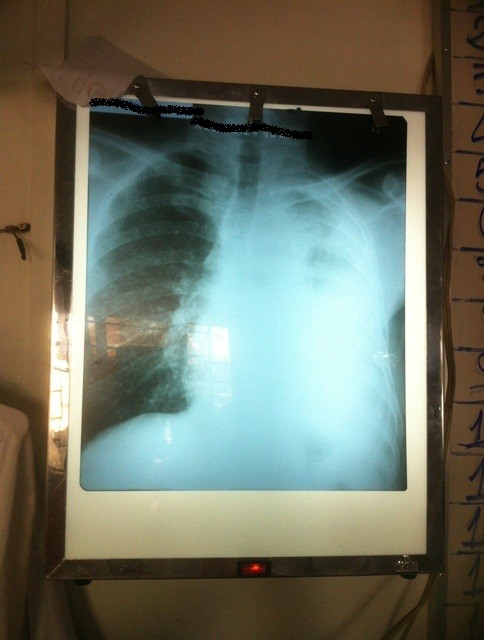

Meanwhile today in my little corner of the world I saw two extraordinary chest x-rays. Both show a whole lung whited out by pleural effusion. This is a rare sight in the First World and would result in each patient being admitted to a high-technology Intensive Care Unit with supported ventilation. Here it is a much more common finding with oxygen administered by nasal prongs the only support available.

This x-ray shows the left lung almost completely “whited out”, filled with fluid probably caused by an infection (but possibly another cause, eg cancer).